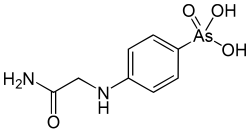

Nach seiner Rückkehr in die Vereinigten Staaten erhielt er im September 1912 eine Anstellung am Rockefeller Institute for Medical Research. Gemeinsam mit Walter Abraham Jacobs und Simon Flexner arbeitete er hier an der Synthese von therapeutisch nutzbaren Arsenverbindungen.[6] Während des Ersten Weltkrieges bildete Michael Heidelberger ab 1915 als Offizier des Medical Corps der United States Army am Rockefeller Institute Ärzte und technische Assistenten in Laborarbeit aus.[6] Darüber hinaus setzte er seine Forschungsarbeiten zur Wirkstoffsynthese fort. Nach dem Ende des Krieges wandten sich Michael Heidelberger und Walter Jacobs neuen Forschungsthemen zu. Während dieser Zeit entwickelte er im Rahmen von Studien zu Blutfarbstoffen mit der Kühlzentrifuge ein Laborgerät, das bis in die Gegenwart von verschiedenen Herstellern produziert wird und weltweit in Laboren im Einsatz ist.[1] Von der Firma, welche die Vermarktung des Geräts übernahm, erhielt er 50 US-Dollar für das Schreiben der Bedienungsanleitung.[7] Kurze Zeit später begann er mit Karl Landsteiner, der im Jahr 1922 an das Rockefeller Institute gewechselt war, sowie mit Oswald Avery und Walther F. Goebel, die am Institut Pneumokokken erforschten, bei der Untersuchung der chemischen Eigenschaften von Polysacchariden aus der Kapsel von Bakterien zusammenzuarbeiten.

In der ersten Phase von Michael Heidelbergers Karriere bis etwa zur Mitte der 1920er Jahre war er als Mitarbeiter des Rockefeller Institute in verschiedenen Projekten tätig. Ausgehend von seiner Ausbildung in organischer Chemie beschäftigte er sich zunächst vor allem mit der Synthese von Wirkstoffen zur Therapie von Infektionskrankheiten wie Syphilis und Poliomyelitis. Im Rahmen dieser Arbeiten trug er zur Entwicklung der Substanz Tryparsamid bei, die erfolgreich zur Therapie der in Afrika weitverbreiteten Schlafkrankheit eingesetzt werden konnte und außerdem in den USA zeitweise gegen die durch Treponema pallidum ausgelöste Neurosyphilis angewendet wurde. Gemeinsam mit Walter Jacobs veröffentlichte er während dieser Zeit rund 50 Publikationen, unter anderem in Fachzeitschriften wie dem Journal of Biological Chemistry und den Proceedings of the National Academy of Sciences.[14] Außerdem gelang es ihm zusammen mit Walter Jacobs, die im Labor von Paul Ehrlich zum Beginn des 20. Jahrhunderts entwickelte Synthese von Arsphenamin zu reproduzieren, einer Substanz zur Behandlung von Syphilis.[21] Weitere Arbeiten aus dieser Zeit betrafen Studien zu Herzglykosiden und zu Chininderivaten[22] sowie zur chemischen Analytik. 1923 erschien ein von ihm verfasstes Laborhandbuch der organischen Chemie.